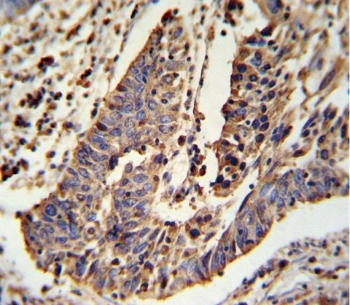

Supportive validation

- Submitted by

- NSJ Bioreagents (provider)

- Main image

- Experimental details

- IHC testing of FFPE human lung carcinoma tissue with SCNN1A antibody. HIER: steam section in pH6 citrate buffer for 20 min and allow to cool prior to staining.